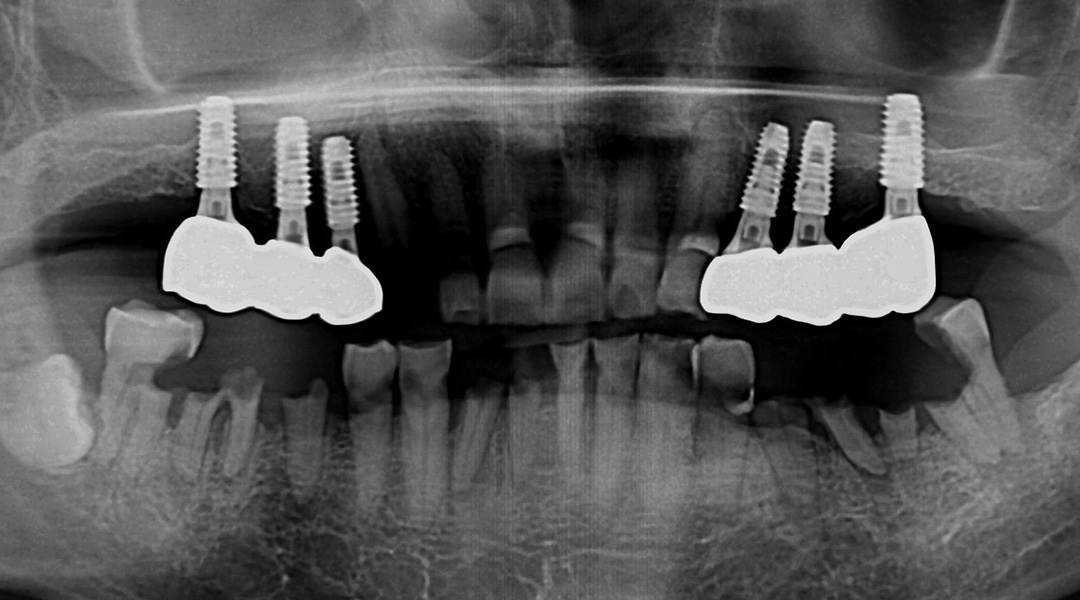

BEFORE & AFTER

갤러리치과의원의 전후 사진을 확인해보세요.

- 무통임플란트